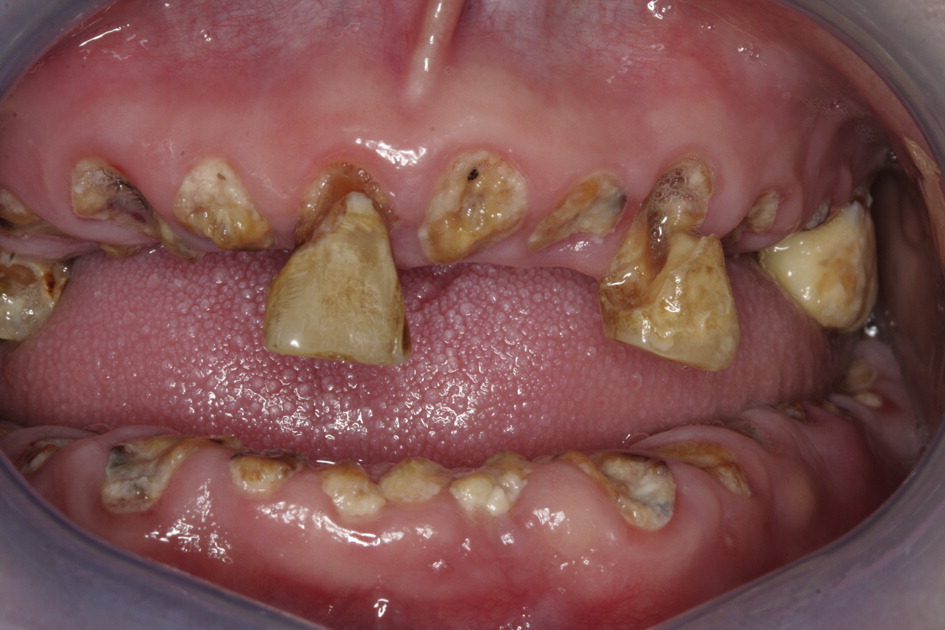

Methamphetamine abuse can affect oral hygiene, causing decay and gum disease. This condition is often referred to as “Meth mouth.”

- The severe tooth decay and gum disease caused by meth abuse can often lead to teeth falling out or breaking off and almost always bad breath

- This extensive tooth decay is likely caused by a combination of factors such as lack of concern over hygiene due to being high, poor nutrition, clenched jaws, grinding teeth, indulging in other activities that are bad for dental hygiene

The severe tooth decay and gum disease caused by meth abuse can often lead to teeth falling out or breaking off and almost always bad breath. An examination of over 550 meth abusers found that:

- 96% had cavities

- 58% had untreated tooth decay

- 31% had six or more missing teeth

Symptoms of meth mouth often include teeth being blackened, stained, rotting, crumbling, and falling apart. In most instances, the affected teeth cannot be salvaged and will result in tooth extractions. This extensive tooth decay is likely caused by a combination of factors such as lack of concern over hygiene due to being high, poor nutrition, clenched jaws, grinding teeth, indulging in other activities that are bad for dental hygiene (smoking cigarettes, sugary beverages, etc.), and other physiological and psychological changes caused by abuse.